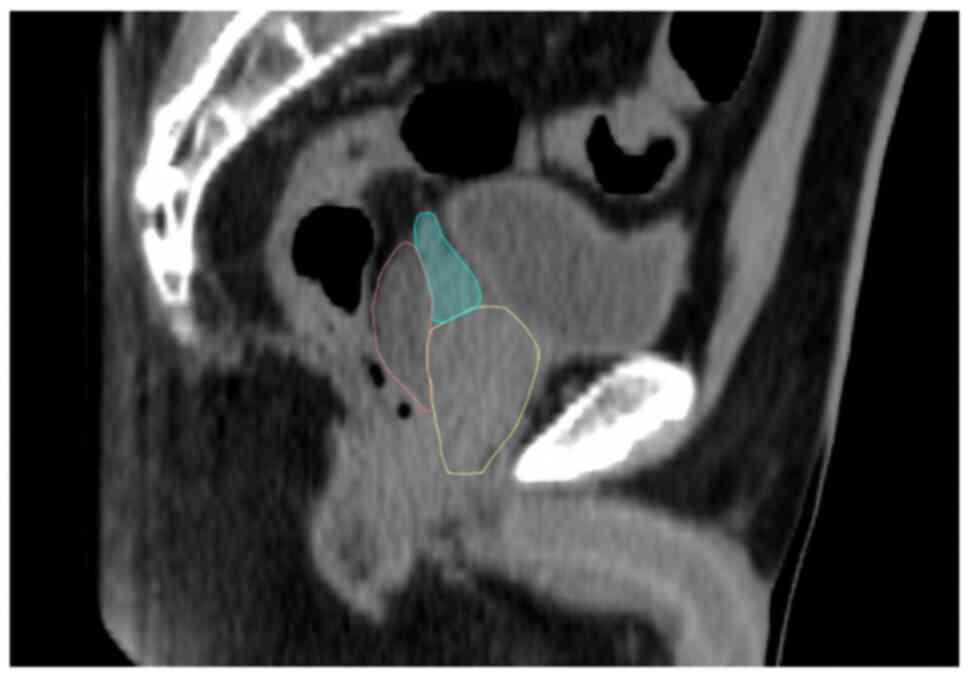

Relationship between seminal vesicle displacement and distribution of hydrogel spacer within the perirectal space in prostate radiotherapy

The influence of a hydrogel spacer (HS) on seminal vesicle (SV) displacement in prostate radiotherapy was examined in the present study. A total of 20 patients with prostate cancer, who received intensity‑modulated radiation therapy (IMRT), were enrolled. Computed tomography and magnetic resonance imaging were performed before and after HS insertion within the peripheral space for IMRT planning. Before and after HS insertion, The SV was delineated, and the amount of SV displacement was evaluated. Large SV cranial displacements (≥0.50 cm) were observed in 25% of patients. A HS lateral distribution of ≥1.00 cm in the upper two slices (midgland + superior) influenced the SV cranial displacements (P<0.01) and was associated with large SV cranial displacements (≥0.5 cm) (P<0.01). The HS cranial distribution in the upper slices did not influence SV cranial displacements (P=0.16). In addition, any HS lateral distribution of ≥1.00 cm in all slices did not induce the SV lateral and anterior‑posterior displacements (P=0.50 and 0.70, respectively). In conclusion, SV cranial displacement was influenced by HS lateral distribution of ≥1.00 cm in the upper two slices. Therefore, when the sigmoid colon or small bowel is depressed in rectovesical excavation and SV needs to be included in the target volume, HS insertion should be performed carefully.

Figure 1